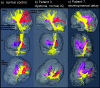

Background and purpose: Conventional MR imaging shows evidence of brain injury and/or maldevelopment in 70%-90% of children with cerebral palsy (CP), though its capability to identify specific white matter tract injury is limited. The great variability of white matter lesions in CP already demonstrated by postmortem studies is thought to be one of the reasons why response to treatment is so variable. Our hypothesis is that diffusion tensor imaging (DTI) is a suitable technique to provide in vivo characterization of specific white matter tract lesions in children with CP associated with periventricular leukomalacia (PVL).

Materials and methods: In this study, 24 children with CP associated with PVL and 35 healthy controls were evaluated with DTI. Criteria for identification of 26 white matter tracts on the basis of 2D DTI color-coded maps were established, and a qualitative scoring system, based on visual inspection of the tracts in comparison with age-matched controls, was used to grade the severity of abnormalities. An ordinal grading system (0=normal, 1=abnormal, 2=severely abnormal or absent) was used to score each white matter tract.

Results: There was marked variability in white matter injury pattern in patients with PVL, with the most frequent injury to the retrolenticular part of the internal capsule, posterior thalamic radiation, superior corona radiata, and commissural fibers.

Conclusion: DTI is a suitable technique for in vivo assessment of specific white matter lesions in patients with PVL and, thus, a potentially valuable diagnostic tool. The tract-specific evaluation revealed a family of tracts that are highly susceptible in PVL, important information that can potentially be used to tailor treatment options in the future.